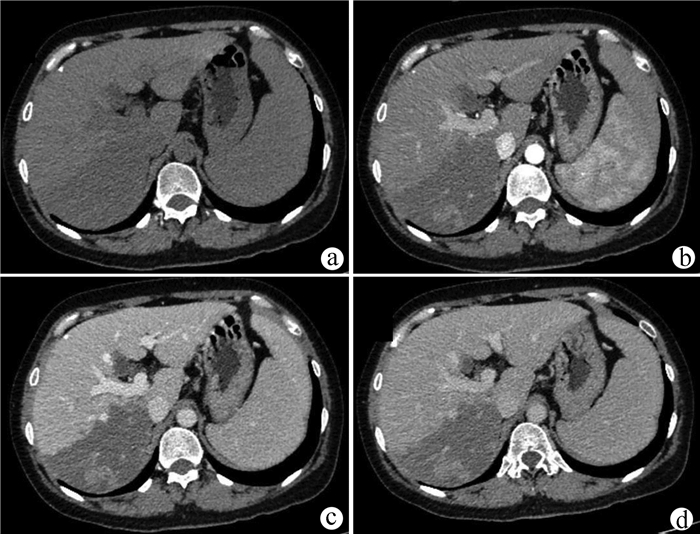

Recurrence after hepatectomy for primary gastrointestinal stromal tumor of the liver: A case report

Kangwei LIU, Xin GENG, Lei WANG, Cijun PENG

2021, 37(12): 2893-2895. DOI: 10.3969/j.issn.1001-5256.2021.12.031

Abstract(939) HTML (236) PDF (2357KB)(47)

Abstract: